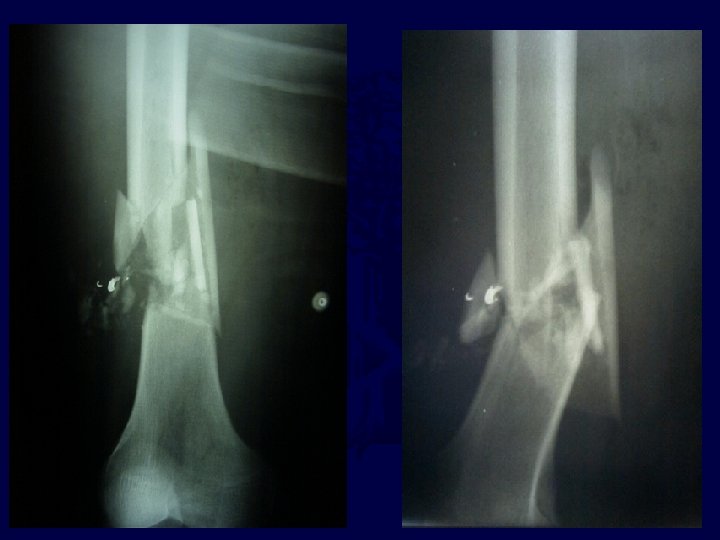

• • 27 y. o. male GSW to right leg ABI =. 7 On table angiogram – Laceration of popliteal artery • Temporizing external fixator placed to stabilize length of limb • Arterial repair performed • Note comminution of fractured femur

Almost Complete Healing by 3, 5 Months